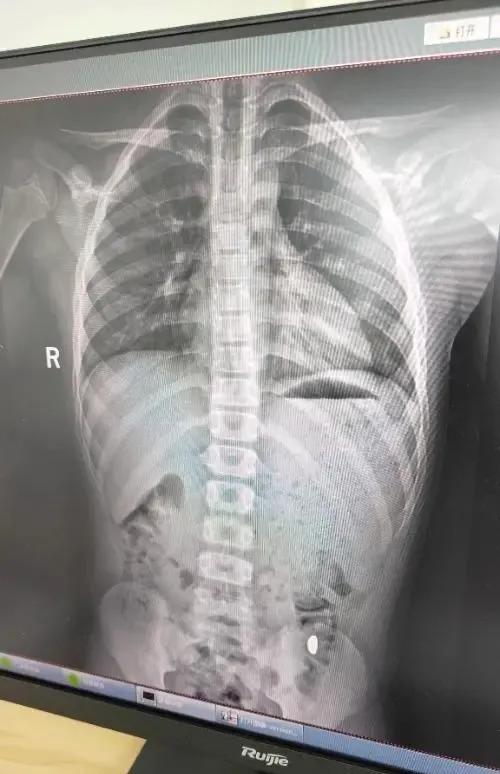

10月26日上午9時,紀女士帶兒子前往昆山市第五人民醫院就診。門診醫生詳細詢問了誤吞時間、物品性質和后續癥狀。體格檢查顯示孩子生命體征平穩,腹部無壓痛。醫生建議進行影像學檢查,X光片清晰顯示胃部存在高密度陰影,確診為金屬異物滯留。

醫生給出兩種處理方案:立即通過胃鏡取出或繼續觀察等待自然排出。考慮到孩子沒有不適癥狀且異物邊緣圓滑,醫患雙方選擇保守治療。醫生開具促進胃腸蠕動的藥物,囑咐如出現腹痛、便血等異常立即復診。紀女士支付了總計386元的檢查費和藥費。